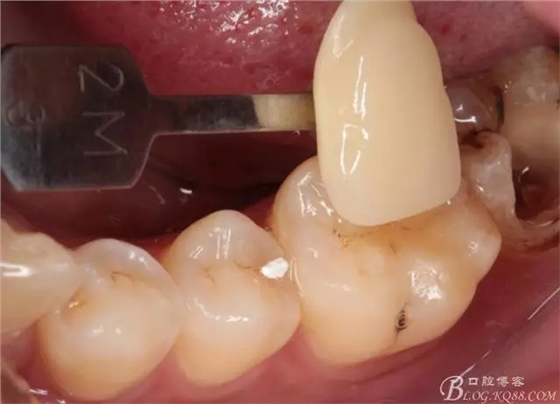

第四次復(fù)診,37叩(—)。此次行冠部修復(fù),因涉及38的拔除,患者不愿拔除,與患者介紹修復(fù)材料與方法,擬37E.max嵌體修復(fù),術(shù)前常規(guī)簽修復(fù)知情同意書。

去除暫封物,拍照,比色。

流動樹脂充填窩洞,金霸王車針和鎢鋼車針常規(guī)備牙,配合硅膠尖拋光,頰側(cè)排00排齦線。硅橡膠二次法取模,記錄咬頜關(guān)系,臨時樹脂充填窩洞。